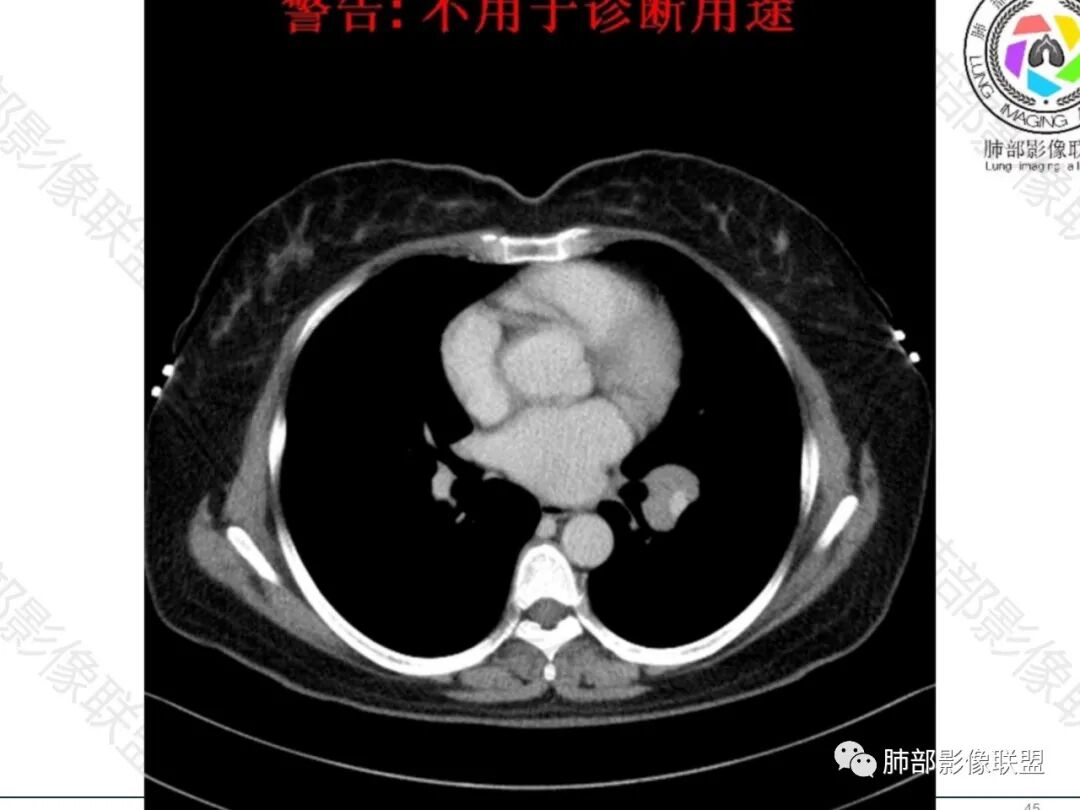

1.中年女性患者,轻咳月余,无咳痰咳血及消瘦等。

2.左肺门见多数增大淋巴结,跨叶分布,上叶支气管轻度狭窄,未见腔内结节或阻塞。

增大淋巴结密度不高,轻度均匀强化,有融合倾向,未见液化,压迫相邻肺动脉且与后者无间隙,左上肺动脉狭窄。

纵隔另见轻度增大淋巴结,梭形密度稍高,边界清楚。

3.双肺未见肺叶体积缩小及明显小叶间隔增厚。双肺上叶偶见微小结节影,边界可分辨,缺乏小叶间隔、胸膜叶间裂或支气管血管束分布趋势。

4.右侧乳腺见软组织密度结节影,边界清楚,未见分叶及毛刺等。

1.单侧肺门多发肿大淋巴结,融合倾向,未见液化,支气管狭窄但未见阻塞,肺动脉受压无间隙,最应当怀疑的是小细胞肺癌,尽管我们在双肺未能搜寻到原发病灶。

让人疑惑的是上下叶的多发,这用一般肺癌的淋巴道转移途径不大好解释。

2.结节病为多系统肉芽肿性疾病,多发且无明显恶性生物学行为为其明显特征,如其较易出现的双侧多发淋巴结增大常有别于肺肿瘤迁徙途径。

当然也可仅仅偏居肺门一隅,本例为左肺门上、下分布。

结节病增大淋巴结常较密实,密度偏高且独立,本例并不典型。双肺也缺乏结节病较特有的小叶间隔及支气管血管束改变特点。